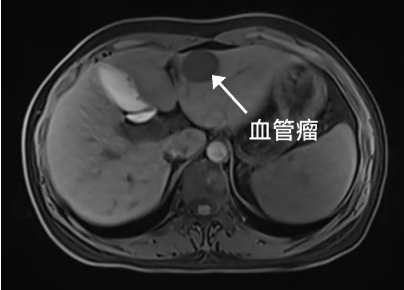

突然发现肝内长了一个

2.9cmm*2.7cm的血管瘤

“肝血管瘤名字里有个“瘤”,是不是就是得了肝癌的意思呀?”刘女士来到卢明柱主任专家门诊焦急地问。别怕,虽然名字里带有“瘤”字,但它并非恶性肿瘤,而是一种常见的肝脏良性肿瘤。“肝血管瘤,它是由肝脏内异常扩张的血管团组成。它通常生长缓慢,大多数情况下无症状,也不会恶变。通常在彩超体检中初步发现,进一步确诊往往需要增强CT或磁共振检查。但没有特效药物治疗。”卢明柱指出。

如何发现与诊断

首选检查:超声检查(安全、无创、便捷),可初步发现血管瘤。

进一步确诊:CT、MRI增强扫描等影像学检查,结合医生专业评估。